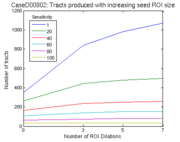

| 02:17, 18 December 2006 | CaseD00802 cingulum.png (file) |  |

4 KB | Image import script | Importing image file | 1 |